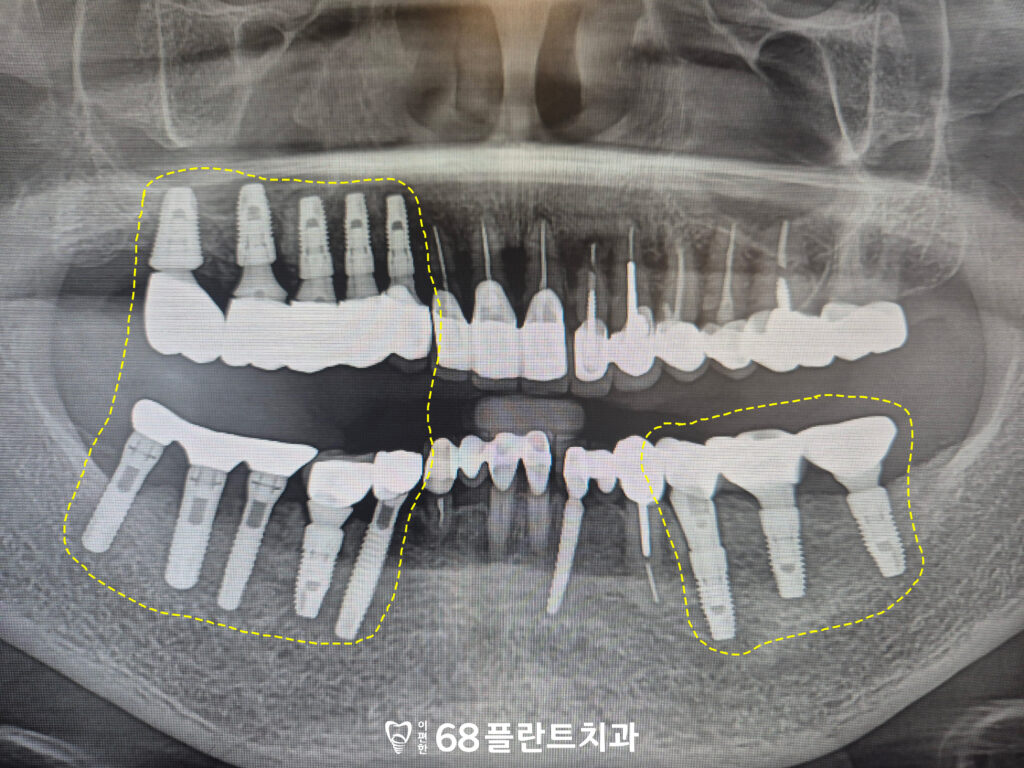

철산역치과 철산역치과

오른쪽 위를 포함하여

양쪽 아래 치아들에서도

치아에 금이 간 상태가

확인되는 상황이었습니다.

또한 기존에 식립되어 있던

임플란트 역시 사용 기간이

상당히 지난 상태로,

보철물과 주변 상태에 대한

확인이 필요한 상황이었는데요.

◆ 전 > 후 ◆

치료 마무리 후 사진입니다.